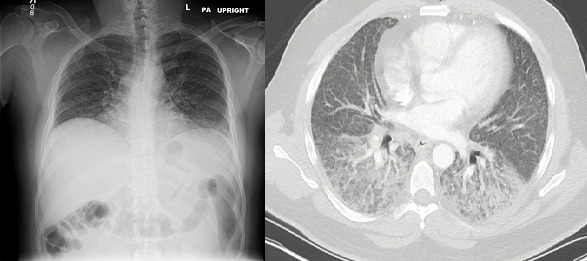

Upon physical examination, temperature was 97.6 ℉, heart rate 106 beats per minute, respiration rate 18 per minute, blood pressure was 128/86 mmHg, oxygen saturation of 88% while breathing ambient air. The patient appeared chronically ill. He was alert and awake. Moist mucous membranes without other lesions were noted in the oral cavity. Cardiac examination was notable for regular tachycardia without cardiac murmurs or extra heart sounds. Pulmonary auscultation was significant for fine inspiratory rales in mid-lung and bases bilaterally. Abdominal examination was unremarkable. No lower extremity edema was noted. Skin and neurological examinations were unremarkable. See Table for relevant laboratory data. See Figure for plain radiograph and computed tomography (CT) of the chest.

Figure. Plain radiograph of the chest (left panel) revealing bilateral interstitial opacities and computed tomography (CT) of the chest (right panel) revealing bilateral basal ground glass opacities.

This patient’s dyspnea on exertion, night sweats, indolent unintentional weight loss, and bilateral pleuritic chest pain with tachycardia and hypoxia raise concern for the clinical diagnosis of pneumonia. Chest x-ray showed bilateral interstitial opacities, most prominently in the medial mid and inferior fields bilaterally; chest CT showed a patulous esophagus, bilateral basal ground glass opacities, interstitial/septal thickening, regions of mild atelectasis, tree & bud opacities bilaterally, and possible bronchiectasis. The imaging findings, which were prominent in gravity-dependent areas of the lung, as well the patulous esophagus, were concerning for chronic aspiration. My working diagnosis became a tracheoesophageal fistula, which is a reported pulmonary complication of fistulizing Crohn’s disease. The diagnosis may be confirmed with an upper gastrointestinal series using thickened water-soluble contrast material, a chest MRI and/or esophageal endoscopy and bronchoscopy.

The patient’s findings were concerning for drug-induced interstitial lung disease (ILD) and my differential included atypical pneumonia and malignancy such as lymphoma. Pulmonary imaging displayed basal and peripheral inflammatory changes with an interstitial pattern as well ground glass opacities. Infliximab has been reported to cause ILD. I am concerned that the patient developed auto-antibodies after his most recent infliximab dose resulting in ILD. Pleuritic chest pain, sore throat and rhinorrhea may also occur as a result of infliximab therapy. I suspect ILD may have progressed in a subacute manner and became severe enough to cause symptoms at the time of presentation. I would want to review previous pulmonary imaging if available. Workup would include holding infliximab, bronchoscopy with bronchoalveolar lavage to rule out infection, and if negative would initiate systemic glucocorticoids.